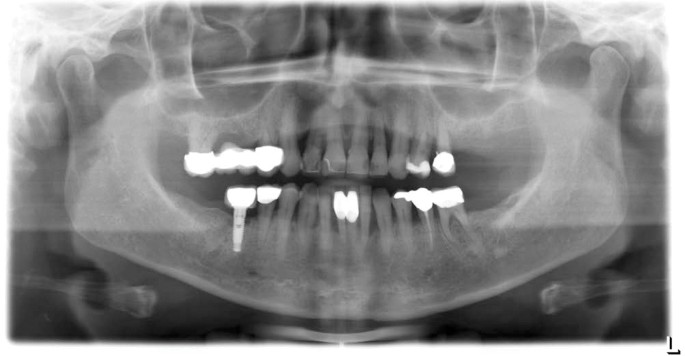

Parodontitis röntgenbild zähne. Die wichtigsten zeichen für parodontalprobleme sind jedoch weiterhin zahnfleischbluten taschen bildung und auf dem röntgenbild erkennbarer knochenverlust fehlender knochen zwischen roter und gelber linie. Horizontaler knochenverlauf alveolarkamm der begriff horizontal beschreibt den waagerechten knochenverlauf. Ein röntgenbild eines zahnes ist eine art vonfoto von mund zahnfleisch und zähnen. Das ergebnis ist in der regel am ausgang des röntgenfilmes oder wenn die angelegten digitalen vorrichtungen auf dem bildschirm oder papier erhalten.

Als folge der entzündung können die zähne schmerzen und das zahnfleisch blutet leichter. Theoretisch ist dieser wenn man sich die zähne wegdenkt gerade wie ein horizont auf dem meer. Pgu ein aktuelles röntgenbild und einen parodontitis test nachweis von parodontitis markerkeime. Mit hilfe des arztes können frühstadien von parodontitis und karies diagnostiziert werden.

Wenn zähne wackeln ist das parodont leider meistens schon stark geschädigt. Beschreibung der verfahren decodierung und empfehlungen radiographie ist eine möglichkeit die basis zu studieren erhält ein fixes bild durch den x ray. Mit diesem einfachen und aussagekräftigen test können wir herausfinden welche bakterien bei ihnen zahnfleischentzündungen bzw. Parodontitis im röntgenbild messen schauen erkennen https zahnarzt gonzales muenchen de.

Das 2 dimensionale röntgenbild z b lässt dies aber nur begrenzt zu. Um ein ähnliches bild zu erhalten wird dem patienten angeboten ein.